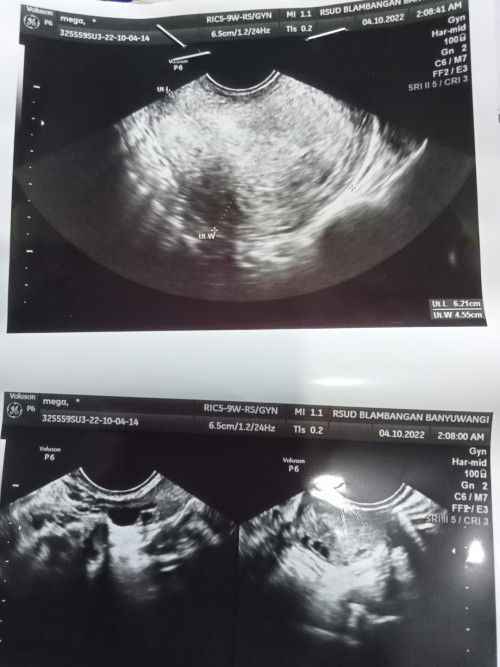

Bund ada yg pernah alami gak seperti aku? USG awal sudah kelihatan kantong janinnya dokter juga bilang klo kandungan nya sehat² aja ,nahhh pas tdi ke RS periksa lgi buat USG entah knpa kantong janinnya tidak terlihat sama sekali terus sudah di suruh pipis kedua kalinya di USG lgi transvaginal tpi tetep aja kantong janinnya gk ada ,di suruh cek laboratorium nyampek sana di suruh nampung pipis tpi hasilnya Alhamdulillah positif ,setelah itu dokter bilang kembali lagi 3 Minggu Minta do'anya ya bunda² semoga 3minggu entar sudah kelihatan janinnya dan kantong janinnya .aminnnnn🤲🥺#seriusnanya #bantusharing #ingintahu